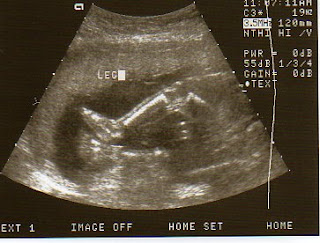

It's a Boy!

We had our ultrasound today, and we found out we are having a boy!!! I'm so excited. I think Spencer was a little excited also.... the minute he found out it was a boy he was texting everyone. I am also measuring 4 days early, so that puts my due date as December 27th, so we are hoping they will let me have him before Christmas. We have a few names that we really like, so I will have to put a poll up and let people vote. Enjoy the pictures.